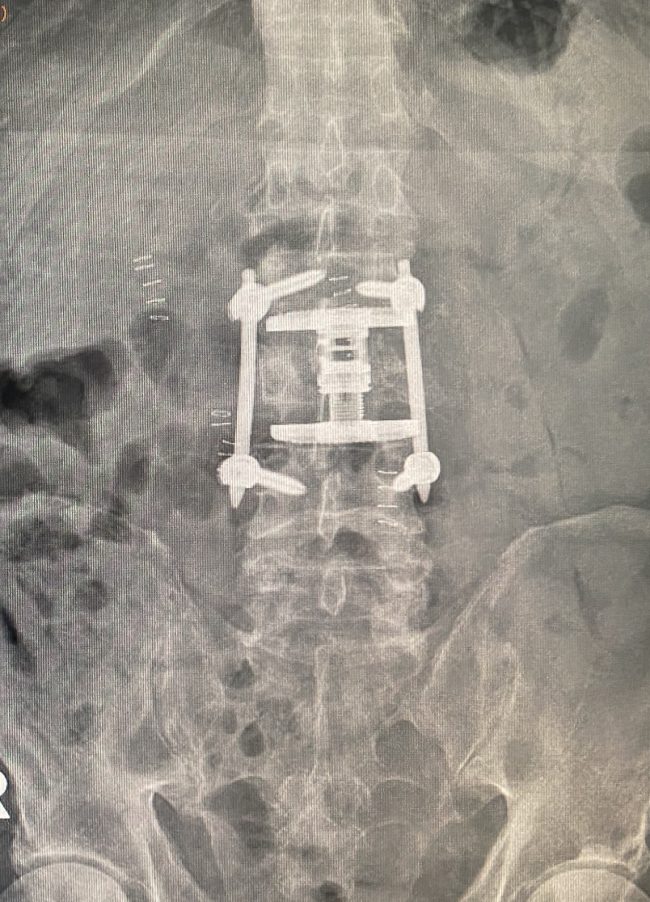

Fuente: Quirónsalud Huelva Es la primera intervención quirúrgica craneal realizada en el Hospital Quirónsalud Huelva Las cefaleas constantes, vértigos, dificultad en la marcha o entumecimiento de los brazos son algunos de los síntomas clásicos en un paciente que sufre la malformación de Arnold-Chiari. El doctor Miguel Ángel Roldán Serrano, neurocirujano del Hospital Quirónsalud Huelva…